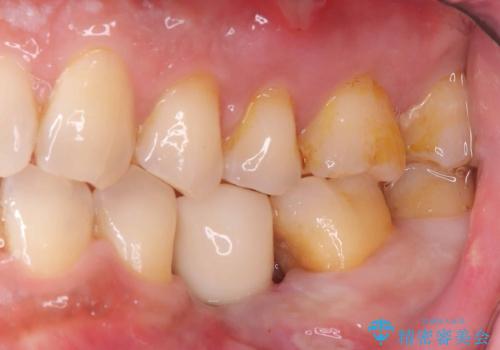

- 20年振りの来院で下顎左右5番にインプラント入れていた患者様です。

右下5番のインプラントは問題ありませんでしたが、左下5番のインプラントがインストール周囲炎に罹患している状態でした。

インプラントを抜去後、再びインプラントで治療を行いました。